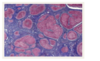

What is the pathophysiology of progression of fibrosis to cirrhosis?

1) Hepatocytes are injured due to infection with a virus, heavy alcohol consumption, toxins, trauma etc, and activates the immune system.

2) Hepatocyte injury stimulates inflammatory immune cells to release cytokines, growth factors etc which direct hepatic stellate cells (source of most ECM) to activate and produce collagen type I and III, glycoproteins, proteoglycans, and other substances

3) These substances are deposited in the hepatic parenchyma and space of disse of the liver, the latter causing capillarisation - where capillaries lose fenestration which blocks exchange (portal hypertension)

4) At the same time, the process of breaking down or degrading collagen is impaired so regeneration is limited to small nodules

What actually is cirrhosis?

Pathological end-stage of any chronic liver disease. Irreversible liver damage with loss of normal liver architecture histologically with bridging fibrosis and nodular regeneration